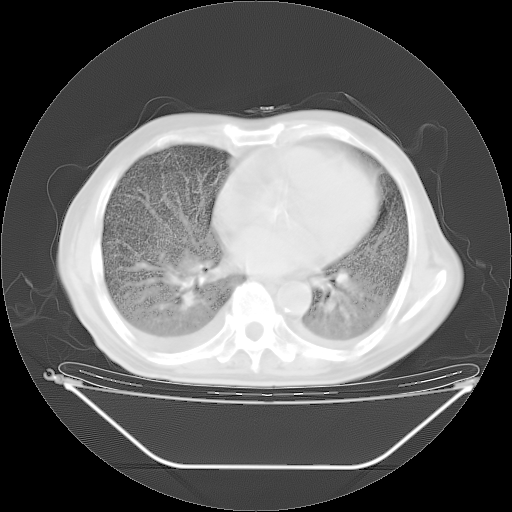

今天复查肺部CT,发现双肺广泛磨玻璃样改变。所以我把3月19日和5月9日相隔50天的肺部CT上传。请大家会诊。

2009年3月19日肺部CT片。

2009年3月19日肺部CT